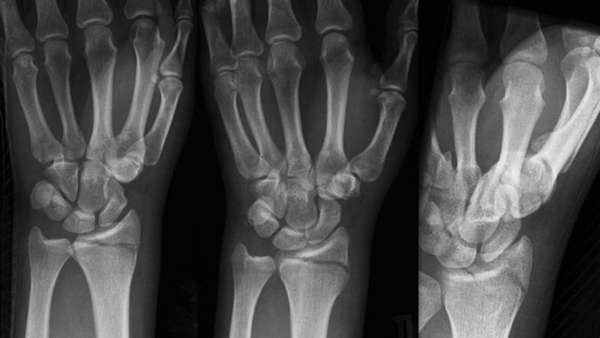

На первоначальном этапе врач собирает анамнез заболевания, в процессе беседы с пациентом уточняет обстоятельства падения и время. Далее производит осмотр, после которого пострадавший направляется на рентгенографию лучезапястного сустава в двух проекциях (прямой и боковой).

Для того чтобы оценить правильность срастания костных отломков, через неделю после травмы и перед снятием гипса назначают контрольную рентгенографию.